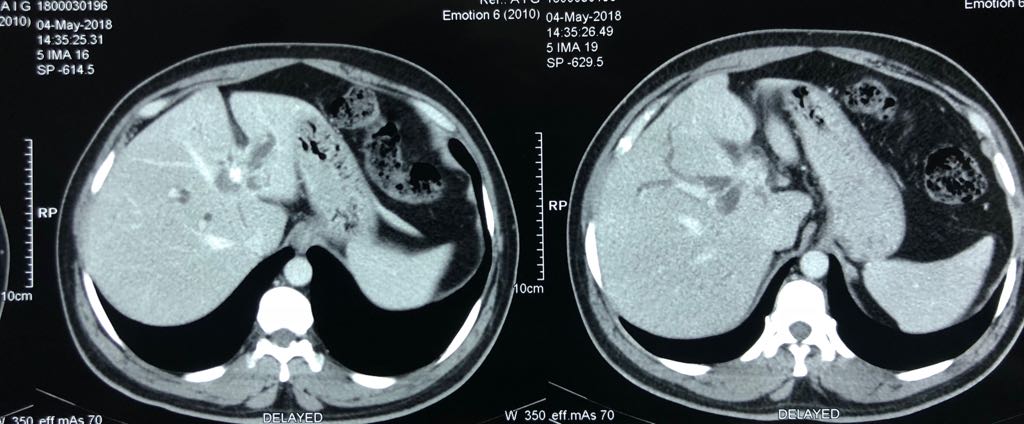

With chemotherapy improved survival with quality of life for Stage 4 cancer patient

Interesting Images March 2019 : Patient came with an early stage carcinoma rectum, underwent Hemicolectomy surgery then lost to follow-up. Later after 9 month patients presented to us with Stage 4 disease (Carcinoma colon with Liver secondaries). Then we started her on treatment with Chemotherapy along with Monoclonal antibodies with six cycle of above said treatment patient achieved near complete remission. We could achieve very good results with chemotherapy even in patients with Stage 4 disease (Carcinoma colon with Liver secondaries).